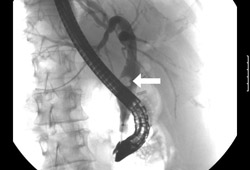

- colangiopancreatografía retrógrada endoscópica (CPRE)

- colangiopancreatografía por resonancia magnética (CPRM)

- colangiografía transhepática percutánea (CTP)